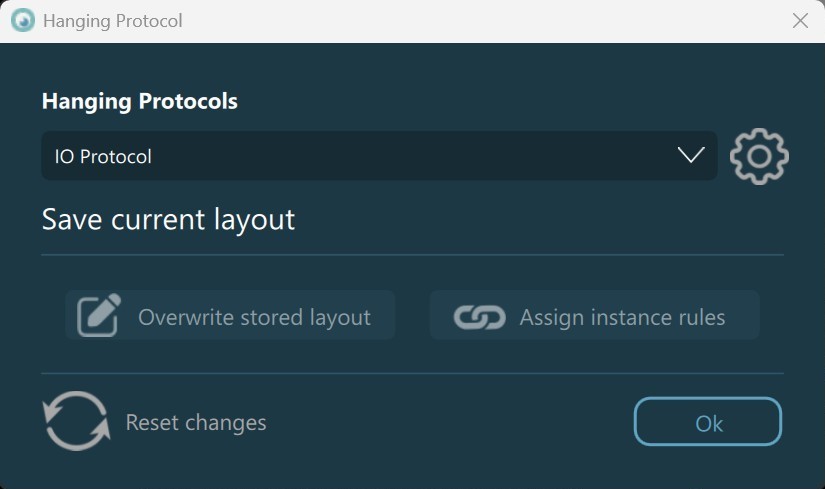

Open Hanging Protocol Dialog¶

Settings icon next to the dropdown. Press Ok to close the dialog.

Overwrite Stored Layout: Overwrite the layout and grid rules for the selected Hanging Protocol. The button becomes enabled when users manually modify the size of the cells in the viewer grid, or when changing the number of rows or columns in the viewer grid from the viewer menu.

Assign Instance Rules: DICOM images can be placed in any cell of the viewer grid once the VisioVIEW Viewer is opened by using the viewer image stack, or by opening them from the series panel. When a Hanging Protocol is active in the Viewer, images that are placed in the grid without meeting the criteria for the Hanging Protocol instance rules can be assigned to the instance rules related to the specific cell based on the selected Hanging Protocol. Once assigned, these instance rules override the specific DICOM tag values in the DICOM file itself.

Reset Changes: Reset any unsaved changes to the layout and grid rules of the selected Hanging Protocol (updated viewer grid, updated cell sizes, and/or reordered or modified images).